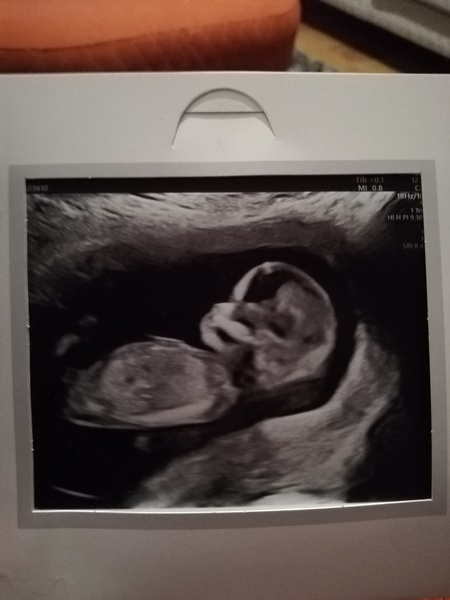

Yes! Everything was fine! Can't believe it! They put me forward by 3 days so I'm 13 weeks 3 days!! Eeeeeeek! Did you have one? Xx

Awwwww @HalGem99 that is the most beautiful scan! So clear!!